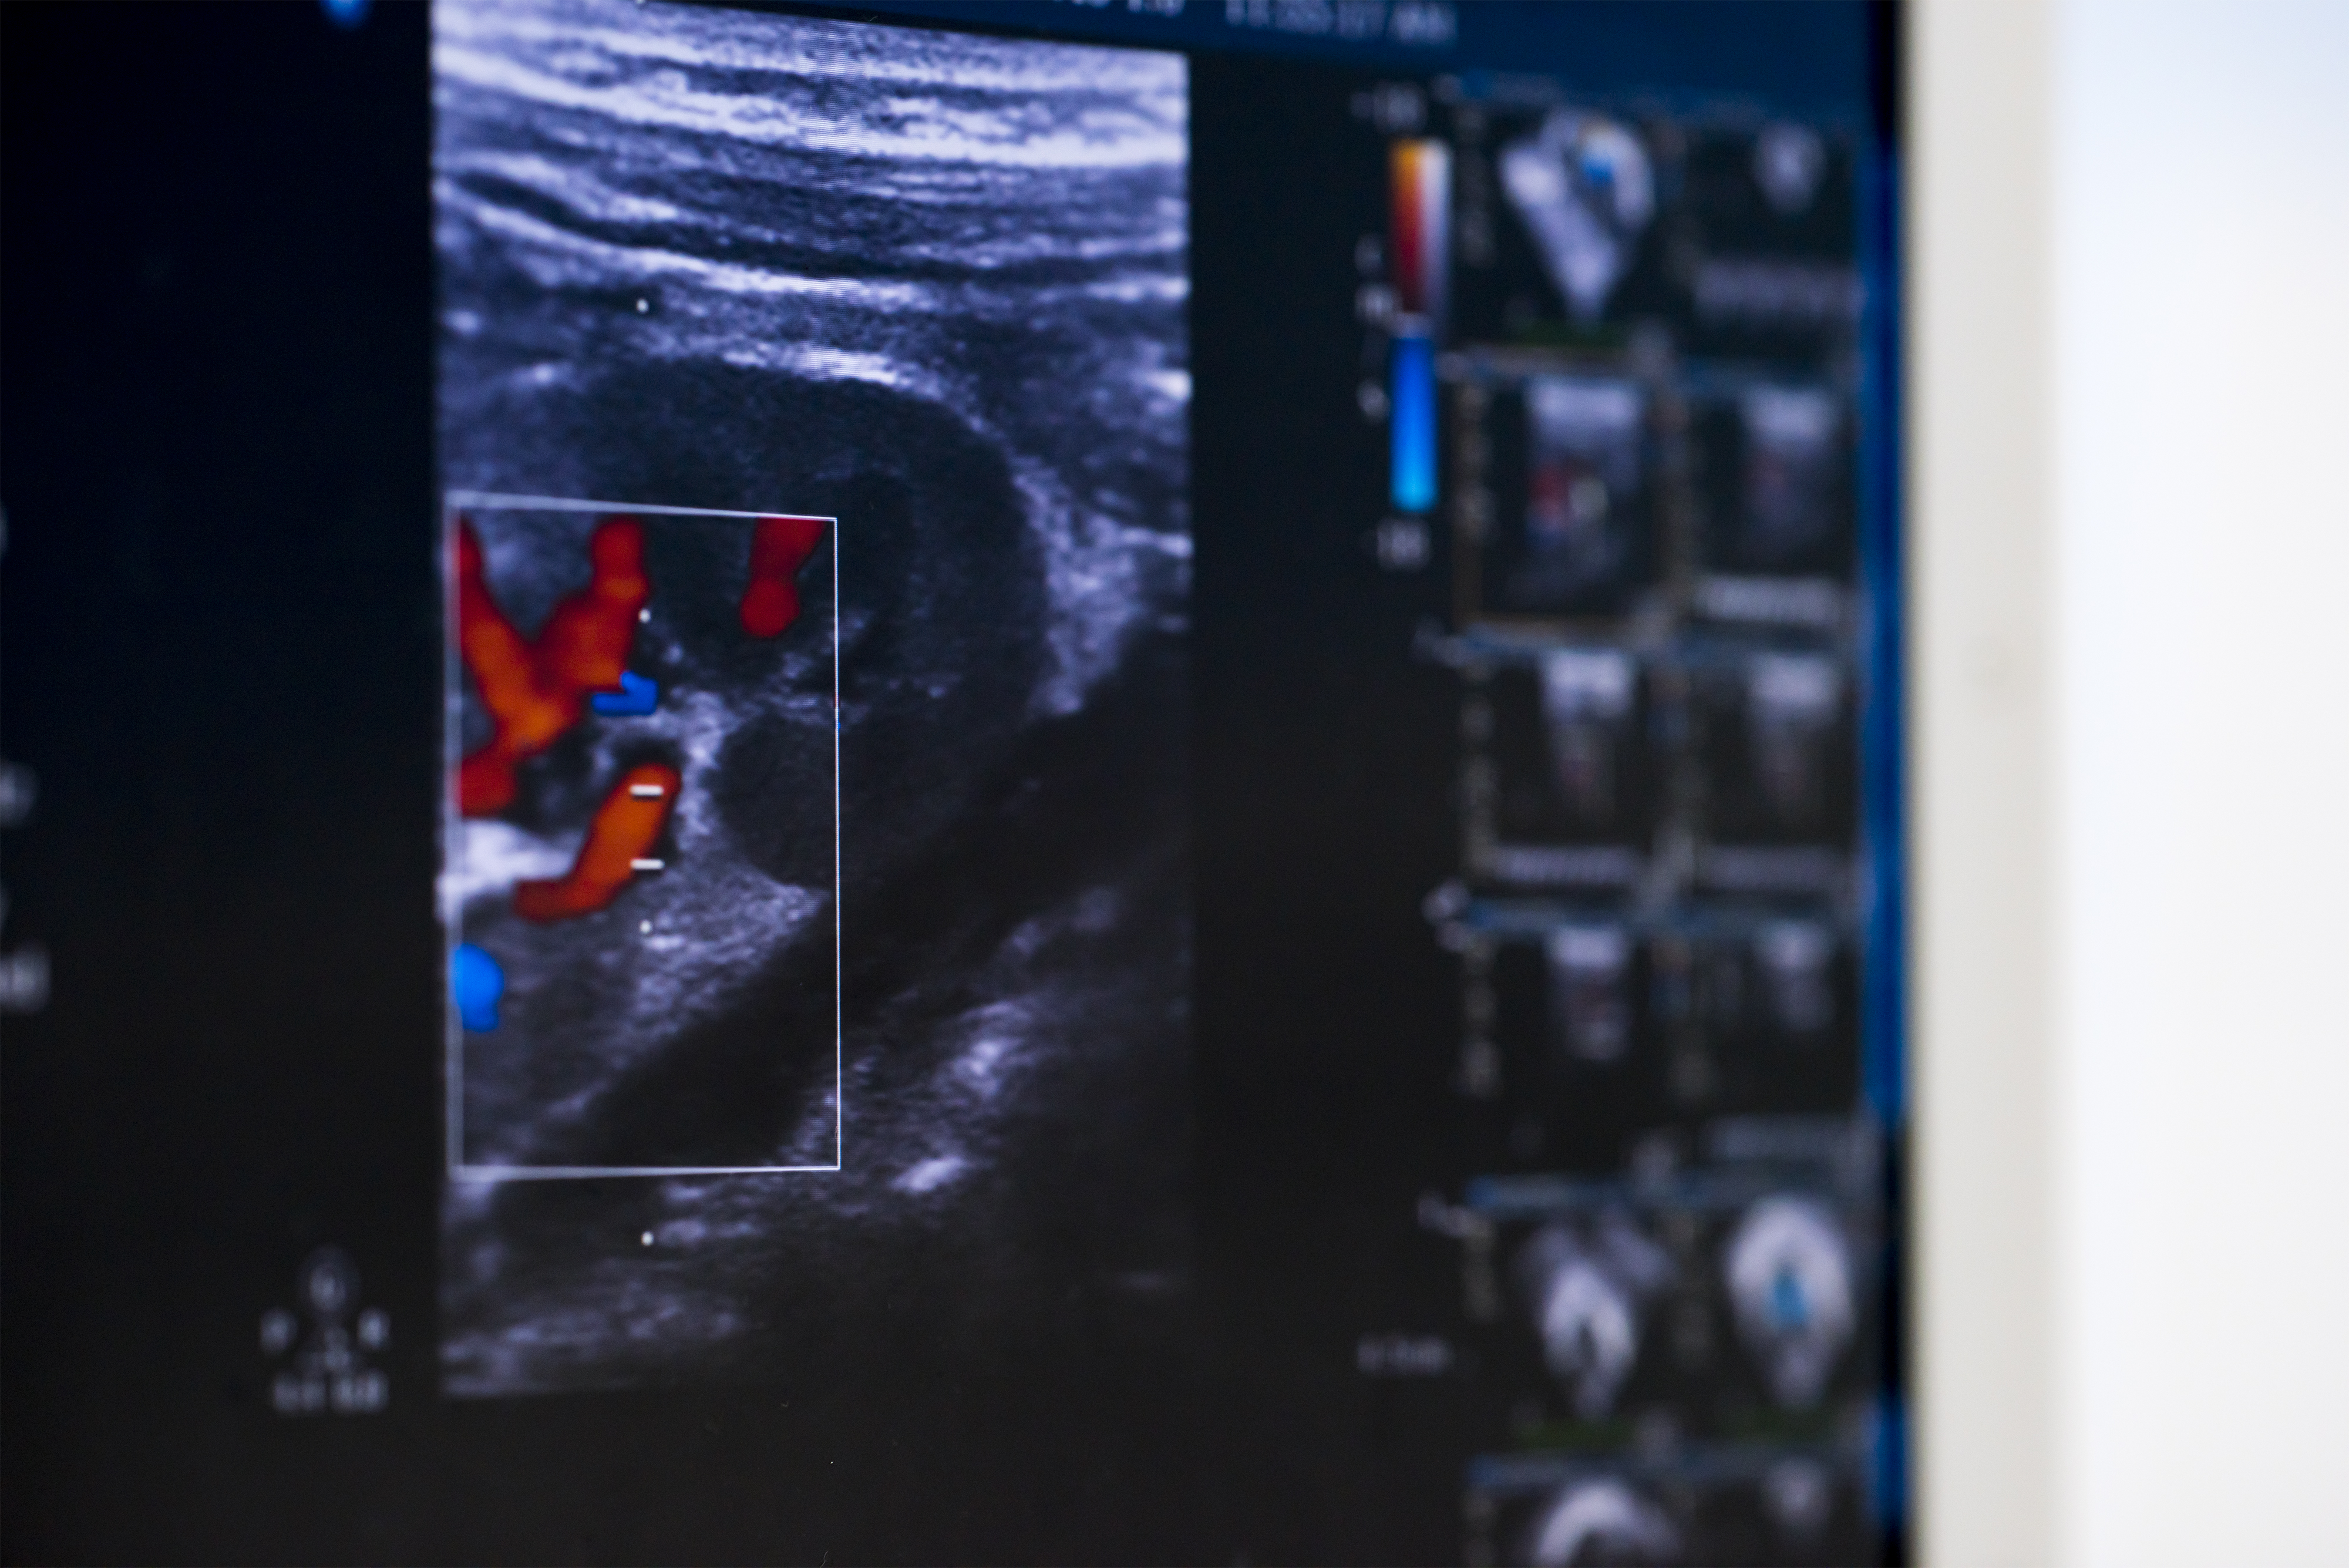

Estenosi aòrtica

És una malformació que es dona progressivament a la vàlvula aòrtica i produeix una obstrucció del flux de sortida del ventricle esquerre. Sovint, l’estenosi aòrtica va associada a més d’un tipus d’obstrucció, com ara l’estenosi de la vàlvula mitral, la coartació aòrtica i l’estenosi aòrtica supravalvular. Això fa que pugui formar part de la síndrome del cor esquerre hipoplàstic.